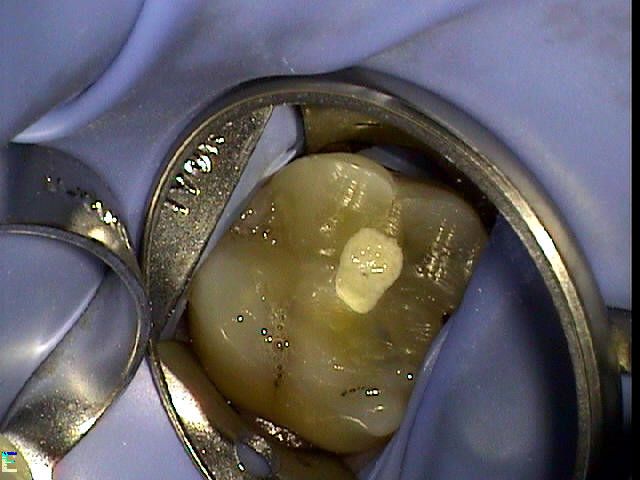

Figure 4 through Figure 10 depict several teeth that have conservative accesses while still allowing the clinician to adequately instrument and clean each tooth to achieve effective root canal therapy. The success of these cases still hinges on the proper cleaning and shaping of the root canal system, and while conservative accesses are desirable, too small of an access can lead to missed canals, poor instrumentation, improper cleaning, and, ultimately, a failed procedure.